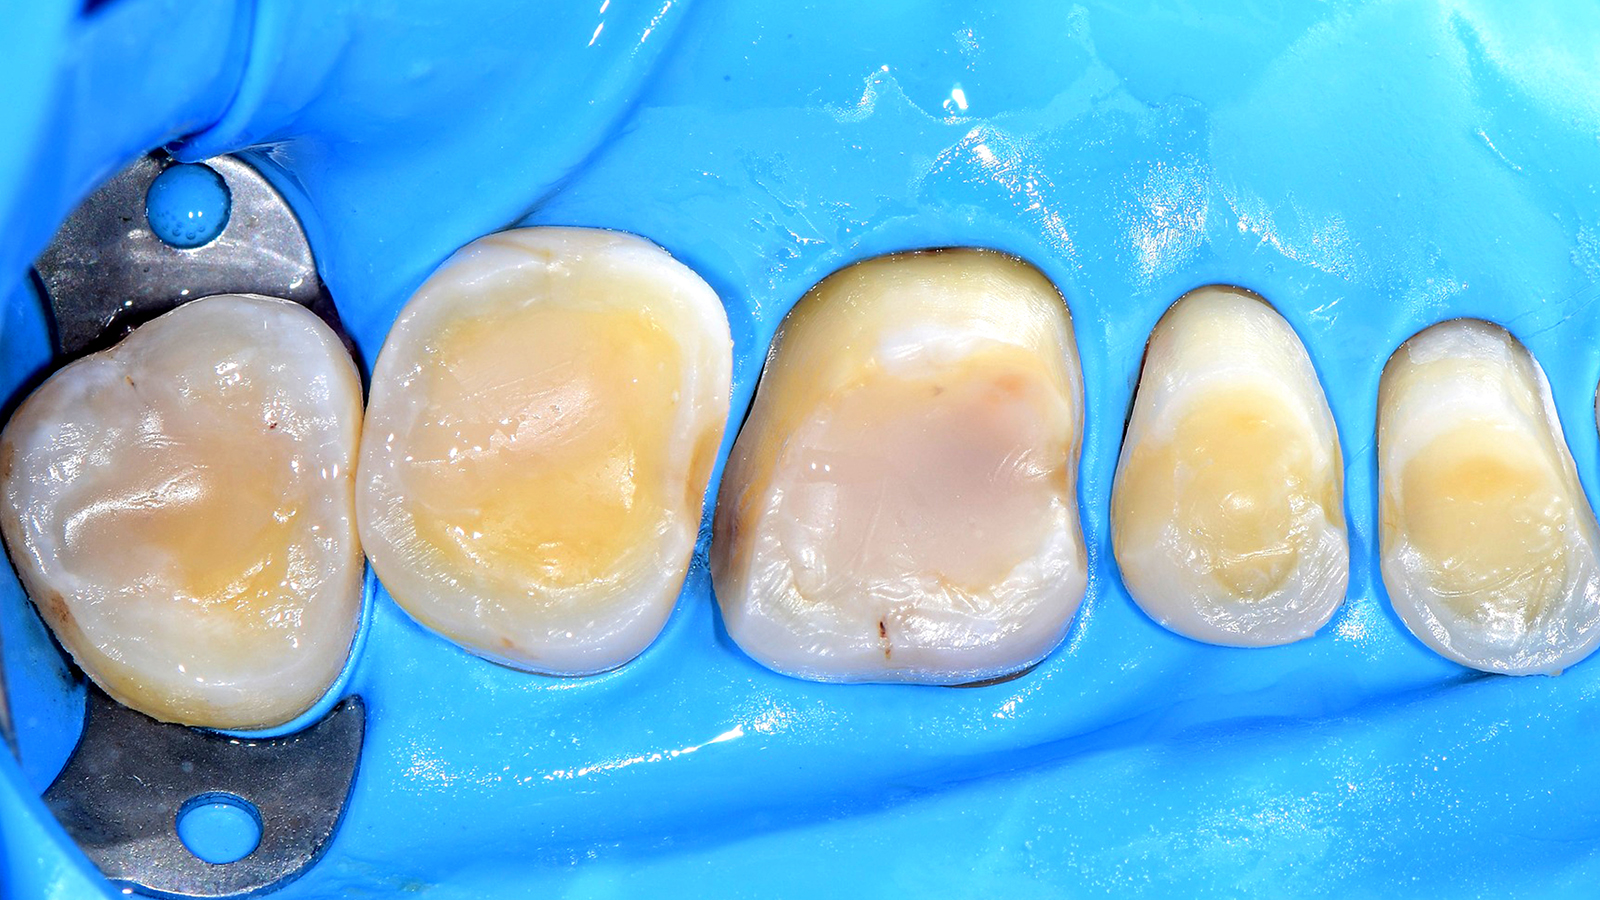

Charisma Bulk Flow ONE combines the self-levelling effect of a flowable material with a high curing depth and good stability after application. This allows to place increments of up to 4 mm inside a cavity. With Charisma Bulk Flow ONE dentists can reduce treatment time without the need for shade selection or the placement of a universal composite as an additional capping layer. With its range of indications from bulk filling through cavity lining to fillings in primary teeth, the efficient restoration procedure is further enhanced by the equally reliable and versatile bonding solution GLUMA Bond Universal.

Using Charisma Bulk Flow ONE without capping layer is beneficial in all clinical cases where a flowable viscosity is ideal during placement, e.g. slot or small cavities or those with tunnel preps, class III restorations with intact labial wall or class V restorations. From a patient perspective, Charisma Bulk Flow ONE is furthermore ideal in cases with little patient compliance or time. By preference or if patients demand a natural morphology, Charisma Bulk Flow ONE can always be used with capping layer, too. Using Charisma Classic, Charisma Diamond or Charisma Topaz on top might be advisable in big cavities or cusp replacements.